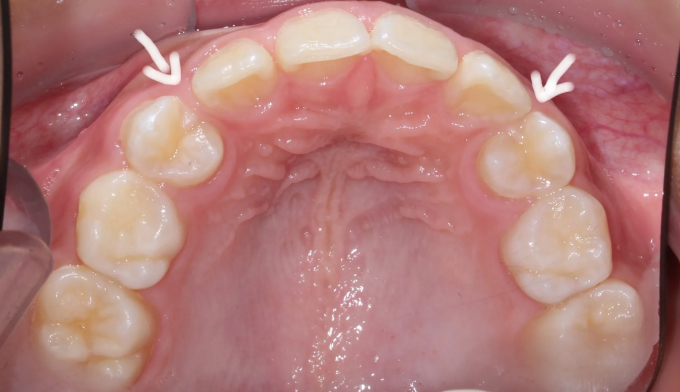

송곳니가 나올 공간이 전혀 없어 보입니다.(화살표로 표시한 부분이 송곳니가 나와야 할 공간입니다)

안모를 고려하여 앞니가 앞으로 뻗치지 않게 주의하면서 어금니만 후방이동시켜 송곳니가 맹출할 공간을 만듭니다.